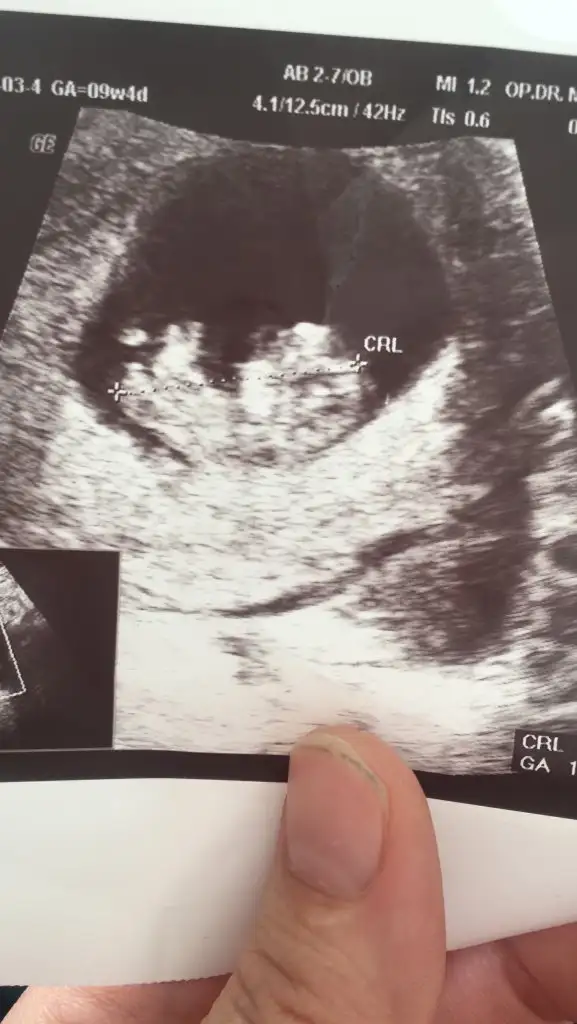

Bana da bakarmısın 11+4 haftalık 🥰 karından bakıldı

Eklentiler

• 554A11E3-2185-45AE-906B-C2E8711D7691.webp

554A11E3-2185-45AE-906B-C2E8711D7691.webp

26,8 KB · Görüntüleme: 150